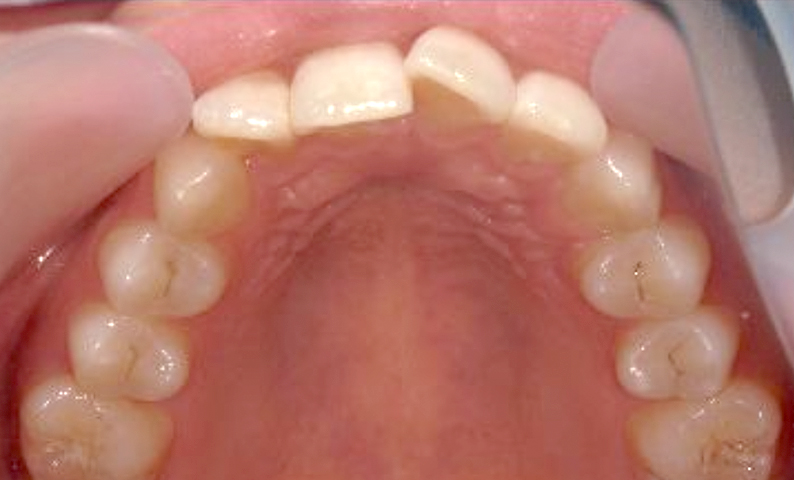

症例_025 上顎だけの部分矯正

治療期間:7ヶ月金額:30万円+税女性前歯のガタガタ上の前歯だけ